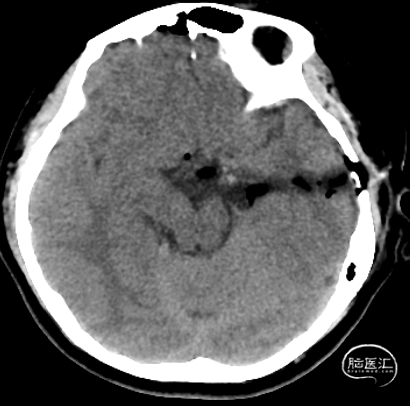

术后影像

2. 术后MRI证实血病灶切除干净;